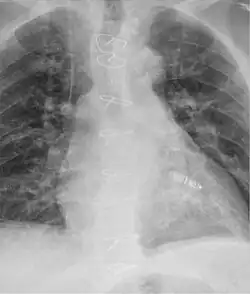

Sztuczny rozrusznik serca (inaczej stymulator serca, kardiostymulator) – urządzenie elektryczne (obecnie wszczepiane w ciało chorego) służące do elektrycznego pobudzania rytmu serca. Stosuje się go, gdy naturalny rozrusznik – węzeł zatokowy, w wyniku różnych schorzeń trwale przestaje spełniać swoją rolę (choroba węzła zatokowo-przedsionkowego), co prowadzi do objawów niedokrwienia mózgu lub niewydolności serca. Drugim wskazaniem do wszczepienia rozrusznika są zaburzenia przewodzenia (tzn. blok przewodnictwa przedsionkowo-komorowego) przez naturalne elektryczne połączenie pomiędzy przedsionkami i komorami serca – węzeł przedsionkowo-komorowy.

Urządzenie stymulujące serce składa się ze stymulatora (aktualnie wielkości mniejszej od pudełka zapałek), zawierającego hermetycznie zamknięte w obudowie z materiałów biologicznie obojętnych baterie, który jest wszczepiany pod skórę. Jest on jednocześnie detektorem, jak i generatorem impulsów elektrycznych. Impulsy mają woltaż rzędu 0,5–5 woltów i czas trwania 0,2–1 milisekundy. W roboczym mięśniu komór serca umieszczane są metalowe elektrody (od 2 do 4) pokryte tworzywem sztucznym. Na ich zakończeniach znajdują się zwykle różnego rodzaju wypustki, ułatwiające fiksację elektrody w pożądanym miejscu.

Wszczepienie (implantacja) kardiostymulatora

Obecnie wszczepianie kardiostymulatorów przestało być domeną kardiochirurgów a stało się zadaniem kardiologów. Zabieg implantacji wykonywany jest w warunkach sali operacyjnej lub pracowni badań inwazyjnych układu krążenia. Sala musi być wyposażona w sprzęt RTG (umożliwiający wykonanie fluoroskopii, koniecznej do kontroli usadowienia elektrody), sprzęt do monitorowania EKG, PSA – Pacing System Analyser – czyli wieloczynnościowe urządzenie pomiarowe umożliwiające pomiar i rejestrację potencjałów wewnątrzsercowych, progu stymulacji i impedancji. Konieczny jest także zestaw narzędzi do wykonania wenesekcji, aparat do echokardiografii oraz sprzęt do perikardiocentezy.

Elektroda zostaje wprowadzona przez żyłę do przedsionka lub komory serca, natomiast drugi jej koniec zostaje doprowadzony do loży stymulatora (zwanej także łożem lub kieszenią), czyli miejsca umieszczenia układu elektronicznego rozrusznika z baterią (zwanego „puszką stymulatora”). U większości osób lożę wytwarza się na mięśniu piersiowym większym. U osób szczupłych lub ze względów kosmetycznych można lożę wytworzyć także pod tym mięśniem. Z przyczyn estetycznych najkorzystniejsze, i dlatego też preferowane u młodych kobiet, jest wykonanie cięcia pod piersią lub w dole pachowym.